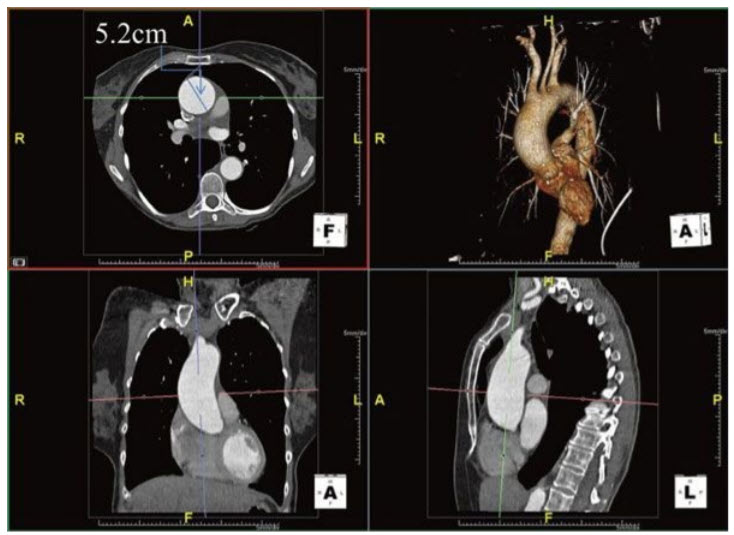

A 32-year-old man with known bicuspid aortic valve is referred to you for management of aortic insufficiency (AI). He is completely asymptomatic and jogs 3 miles a day as well as doing other aerobic exercise for 30 minutes daily. He has a grade III/VI systolic and diastolic murmur at his left sternal border, a collapsing pulse on examination, and his BP 170/70 mmHg. An echocardiogram reveals a mildly dilated LV (end-diastolic dimension of 6.0 cm) with an ejection fraction of 65%. There is prolapse of the conjoined aortic leaflet with 3 to 4+ insufficiency.

The patient undergoes a gated computed tomography angiography of the thorax (Fig. below).